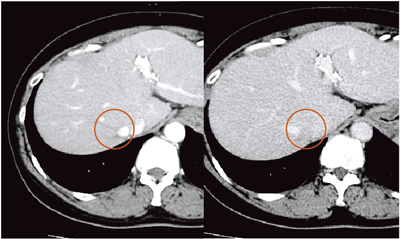

本例は,RFA治療部周囲に再発した例で,まず大動脈を軸に描出し,腹腔動脈,上腸間膜動脈の基始部でRegistrationを行った(図15)。腫瘍部付近にある嚢胞を目安に画像を同期させ,腫瘍部分をターゲットとして指定した後,造影を行って,指定部分が早期相で造影されることを確認した。

図15 症例2:71歳,女性,非B非C型,肝硬変,肝S5,HCC,RFA治療部周囲の再発

本症例は,治療部に近接した局所再発で,治療部と再発部の認識は容易ではなかったが,Smart Fusionを用いることで腫瘍部を明瞭に認識することができた。RFA時も,○で囲まれた部分を目安に穿刺し,確実に焼灼することができた。Smart Fusionは,診断から治療までを支援する有用なツールであると言える。